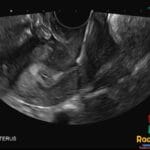

- The “keyhole sign” on ultrasound or VCUG represents the dilated posterior urethra and thickened bladder.

- US: Shows the “keyhole sign” (dilated posterior urethra and bladder), bladder wall thickening, hydroureteronephrosis, and potentially oligohydramnios in the prenatal setting.

- Signs: Keyhole sign: The combination of a dilated posterior urethra and a distended bladder. Dilated posterior urethra with abrupt caliber change: Pathognomonic VCUG finding for valve obstruction.

Question: Which ultrasound finding, consisting of a dilated posterior urethra and bladder, is highly suggestive of this pathology?

The keyhole sign.